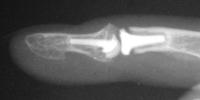

Final implant radiographs.

Xrays one year out.